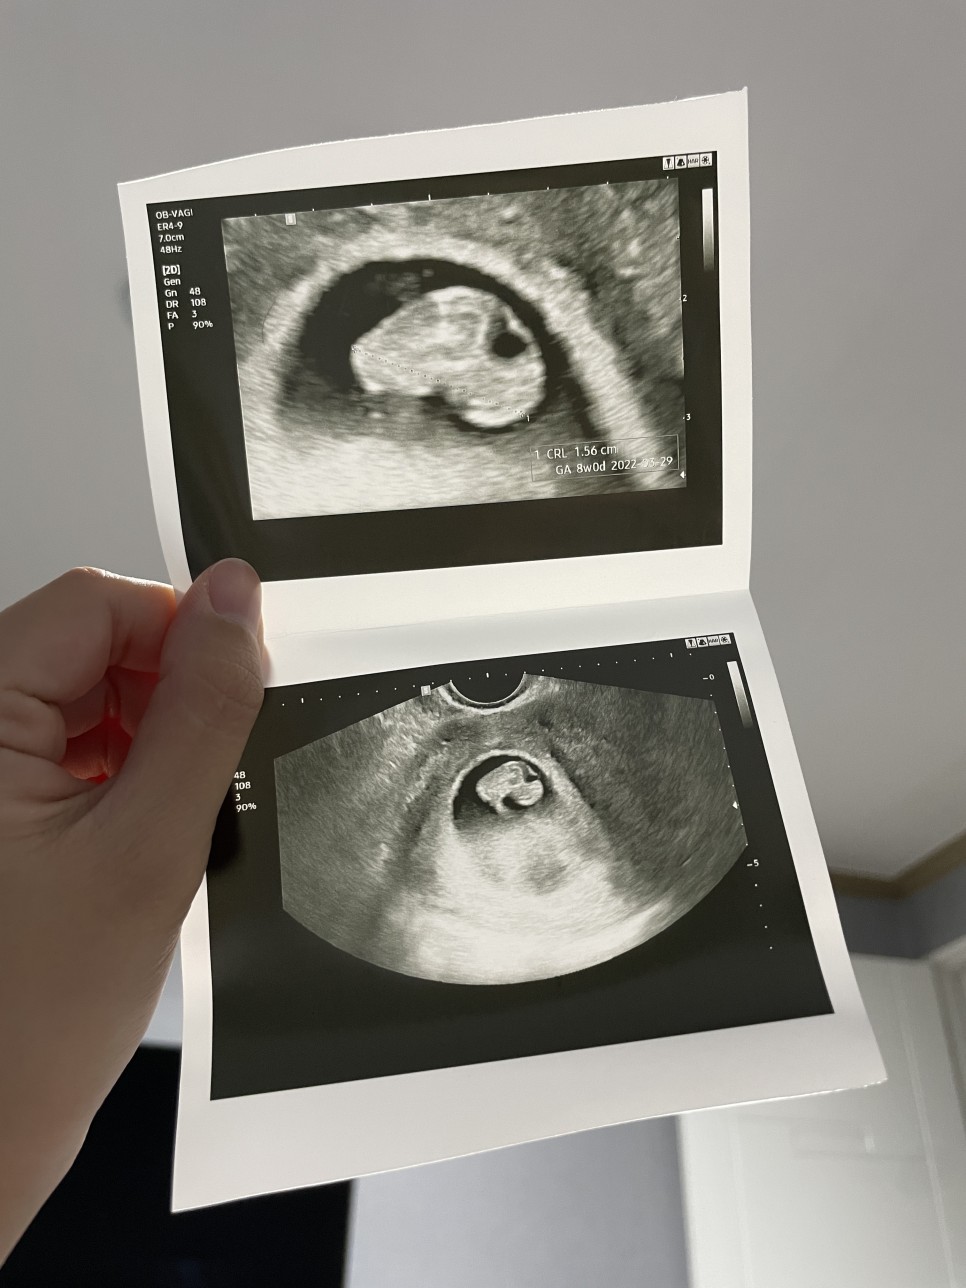

저는 귀여운 젤리곰을 기대 했었는데… 8주차에 젤리곰을 볼 수 있다고 했잖아요 간호사선생님ㅠㅠㅠㅠㅠㅠㅠㅠ(눈물)

과장님 괜찮은데… 초음파는 조금 봐주는 경향이 있는 것 같아ㅠㅠ 초음파 화질도 좋다고는 생각되지 않아서…

그래도… 8주차 주 몇 대에 잘 크고 있다고 하셔서… 안심…